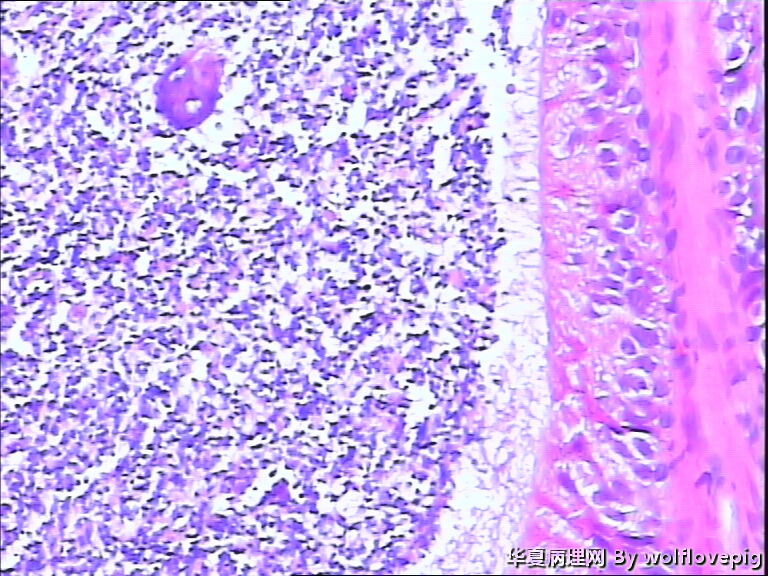

62y,双侧附睾。

临床怀疑结核,以附睾结节切的,取材时未发现明显结节。

精子肉芽肿

精子淤积

送检附睾管囊性扩张,管腔结构较完整,多数管腔内见精子积聚,少数管腔内有出血。

符合精子肉芽肿。

取材切片附睾管扩张,精子淤积,部分区域出血

未见肉芽肿结构,也未见其它异常。

有出血,腔内大量精子,未见特异病变

精子囊肿